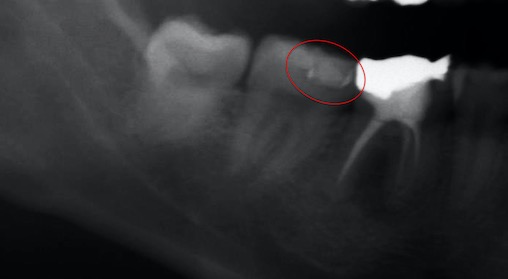

写真(レントゲン写真)

つめ物の下が虫歯になっていました(赤丸部分)。なお、手前の歯は根が膿んでいたため、抜歯をして、矯正治療を行うこととしました。